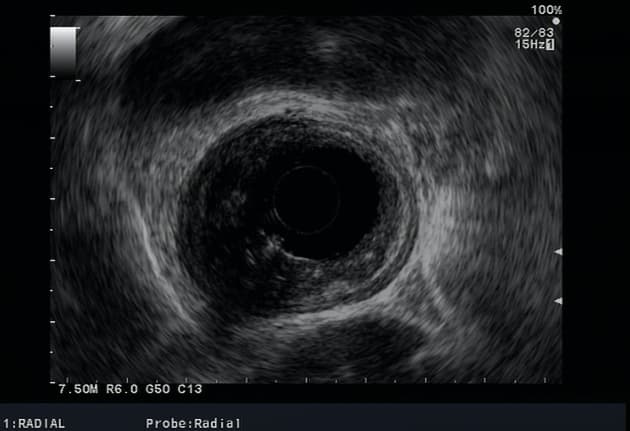

Ca bệnhUng thư thực quản di căn

Ung thư thực quản di căn

Chụp CT đánh giá giai đoạn trong trường hợp ung thư biểu mô tế bào vảy thực quản đã được chẩn đoán.

- Dày thành thực quản đoạn giữa kéo dài.

- Bệnh lý hạch trung thất (lymphadenopathy).

- Nhiều tổn thương di căn hình tròn ở phổi.

- Tổn thương thành thực quản ngấm thuốc thì động mạch (arterial enhancement), phù hợp với bản chất tưới máu trung tâm (centripetal filling).

Ung thư thực quản di căn (Metastatic esophageal carcinoma)

Ung thư thực quản di căn, thường khởi phát từ ung thư biểu mô tế bào vảy hoặc ung thư biểu mô tuyến, biểu hiện với sự lan rộng tại chỗ và di căn xa ở giai đoạn muộn. Trong trường hợp này, tình trạng dày thành thực quản đoạn giữa kéo dài, tăng ngấm thuốc thì động mạch và kiểu lấp đầy hướng tâm rất gợi ý khối u ác tính nguyên phát tại thực quản. Sự hiện diện của hạch trung thất và các nốt phổi hình tròn nhiều ổ xác nhận bệnh lý toàn thân. Các chẩn đoán phân biệt bao gồm ung thư phổi nguyên phát xâm lấn thực quản, u lympho và di căn từ các khối u nguyên phát khác. Chẩn đoán hình ảnh đóng vai trò then chốt trong đánh giá giai đoạn, với CT cho thấy mức độ lan rộng của bệnh và định hướng sinh thiết. Việc phát hiện sớm vẫn còn khó khăn do triệu chứng không đặc hiệu, và tiên lượng thường xấu.